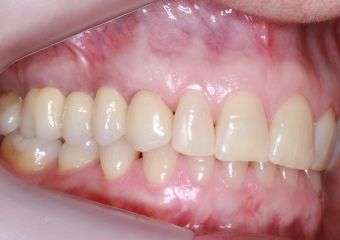

Foto lateral com protese definitiva 22-08-17 - Clínica Cliniface

Foto lateral com protese definitiva 22-08-17